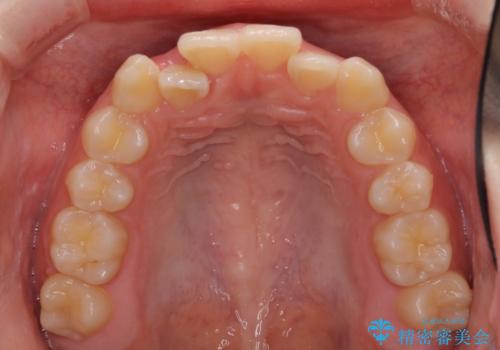

前歯のクロスバイト メタル装置での矯正治療

- 前歯のクロスバイトを気にして来院された患者様です。

前歯の叢生を解消するスペースを獲得するために上顎左右の親知らずを抜歯し、メタルブラケットにて矯正治療を行うこととしました。